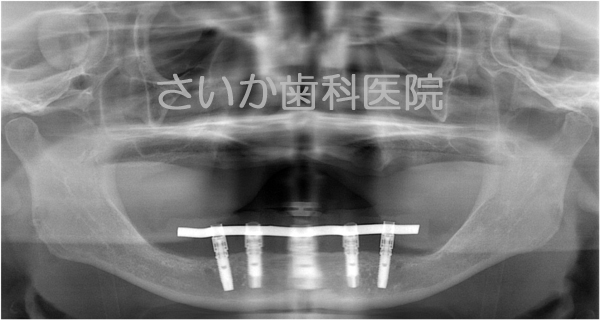

総入れ歯の患者様です。下の入れ歯が安定せず,食事に不自由であるため,インプラント治療を選択しました。

このケースは事前に撮影したCT画像をコンピュータ解析し,歯ぐきを切らずにインプラントを埋め込む方法です(当院の患者様ですが,当院で初めてのケースでしたので奈良県五條市にある中谷歯科医院の堀内克啓先生にご協力いただきました)。

歯ぐきを切らないでインプラントを入れ,その日のうちに「仮の歯」を入れました。写真は手術翌日ですが,歯ぐきの腫れはほとんどありません。食事も柔らかい物であれば手術直後から普通に出来ました。